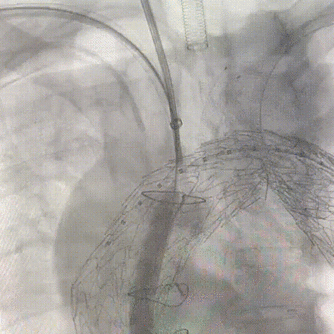

2. 右侧肱动脉置入12Fr鞘至升主动脉,置入Mustang 10mm*80mm球囊,左右颈总动脉置入8Fr鞘。沿加硬导丝置入远端覆膜支架TGU343420定位后释放,继续置入近端覆膜支架TGU404020定位于冠脉吻合口上方释放。

近端支架释放前造影

近端覆膜支架释放